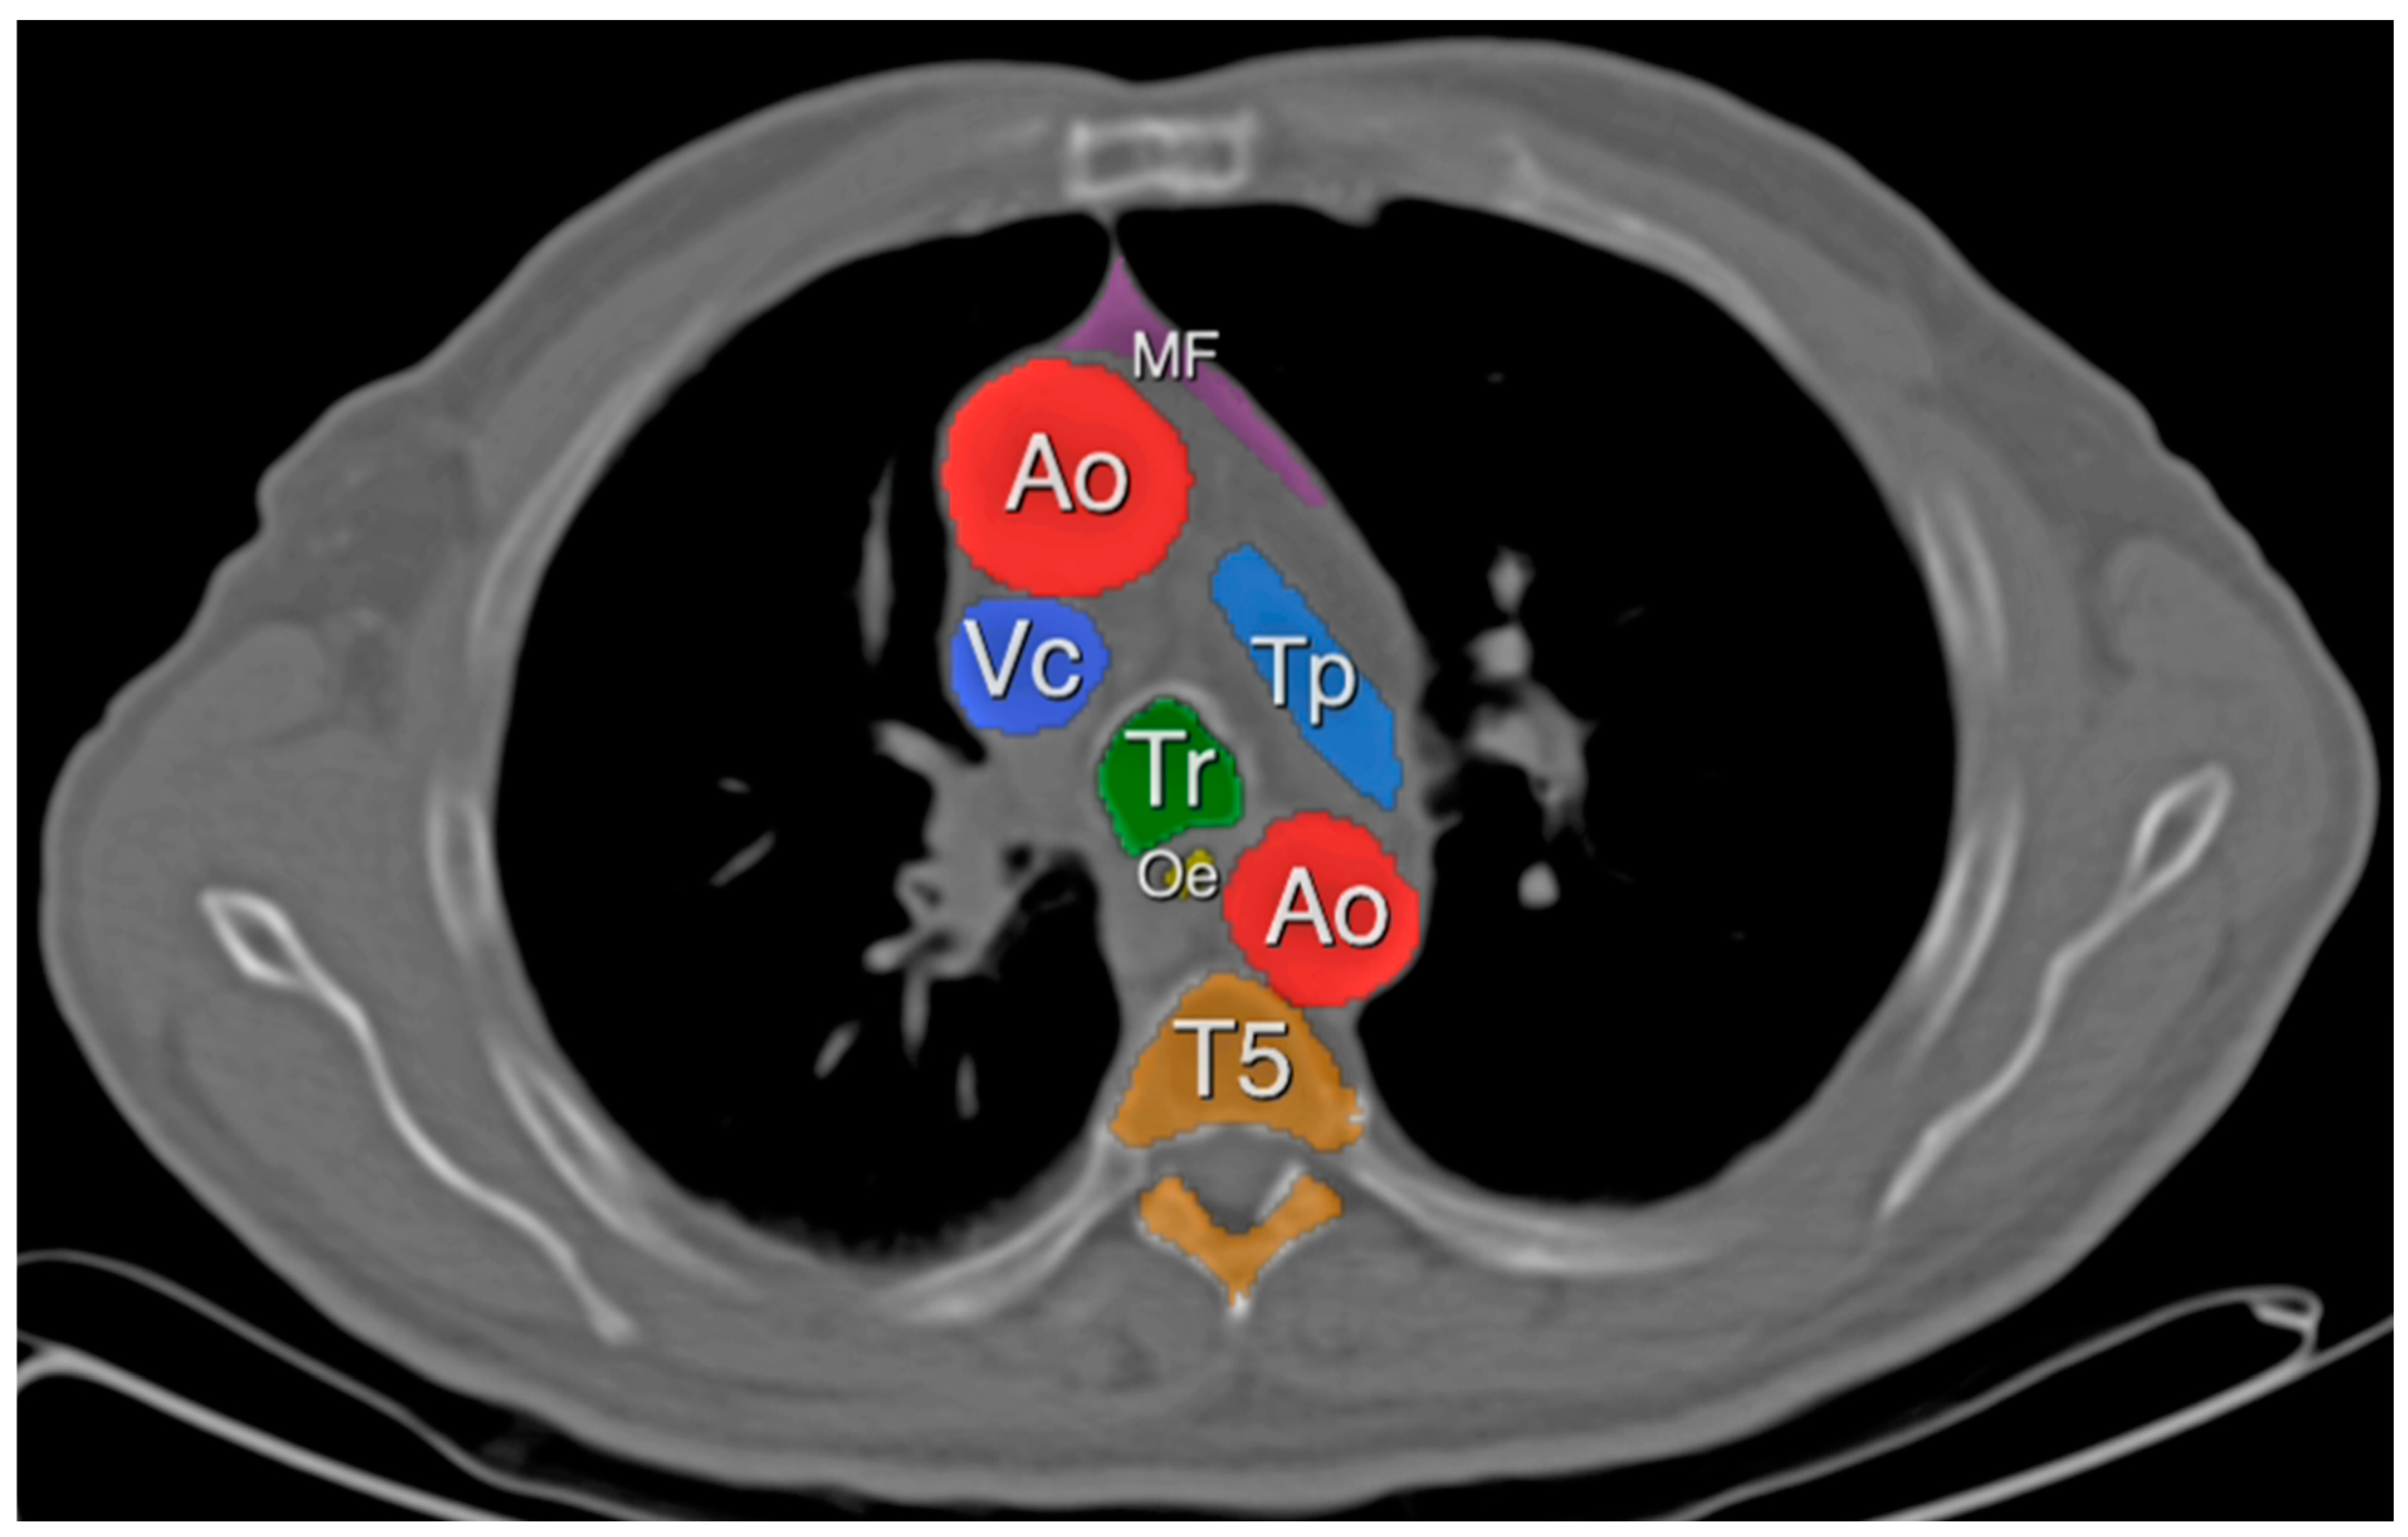

2.3. Definitions